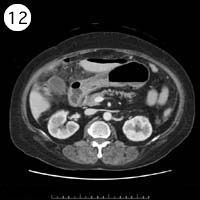

57歳 女性

単純CT

造影CT